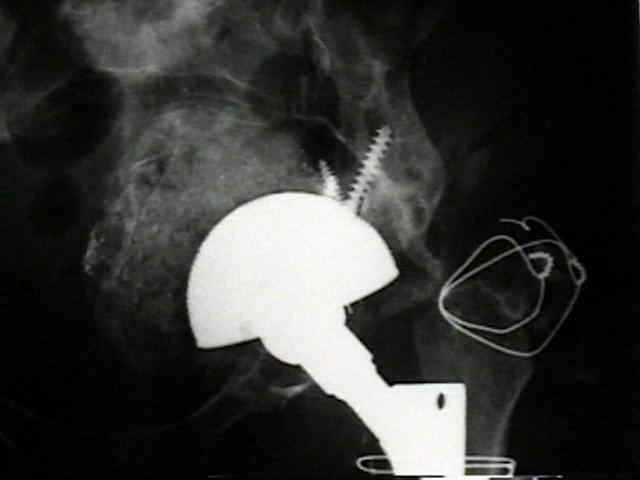

radiographic signs of ingrowth fixation

(from Moore MS, et al.)

- 97 percent of the cups with three or more of these signs were determined to be stable at the time of revision surgery

- in contrast, 83% of the cups with two or fewer signs were loose.

- five radiographic signs of stable cup fixation:

- absence of radiolucent lines

- presence of a superolateral buttress

- medial bone stress-shielding

- radial trabeculae

- inferomedial buttress

radiographic signs of loosening

- radiolucent lines that initially appeared after two years

- progression of radiolucent lines after two years

- radiolucent lines in all three zones

- radiolucent lines 2 mm or wider in any zone

- migration

- loosening is present w/ more than 2 mm of migration (either horizontal or vertical);